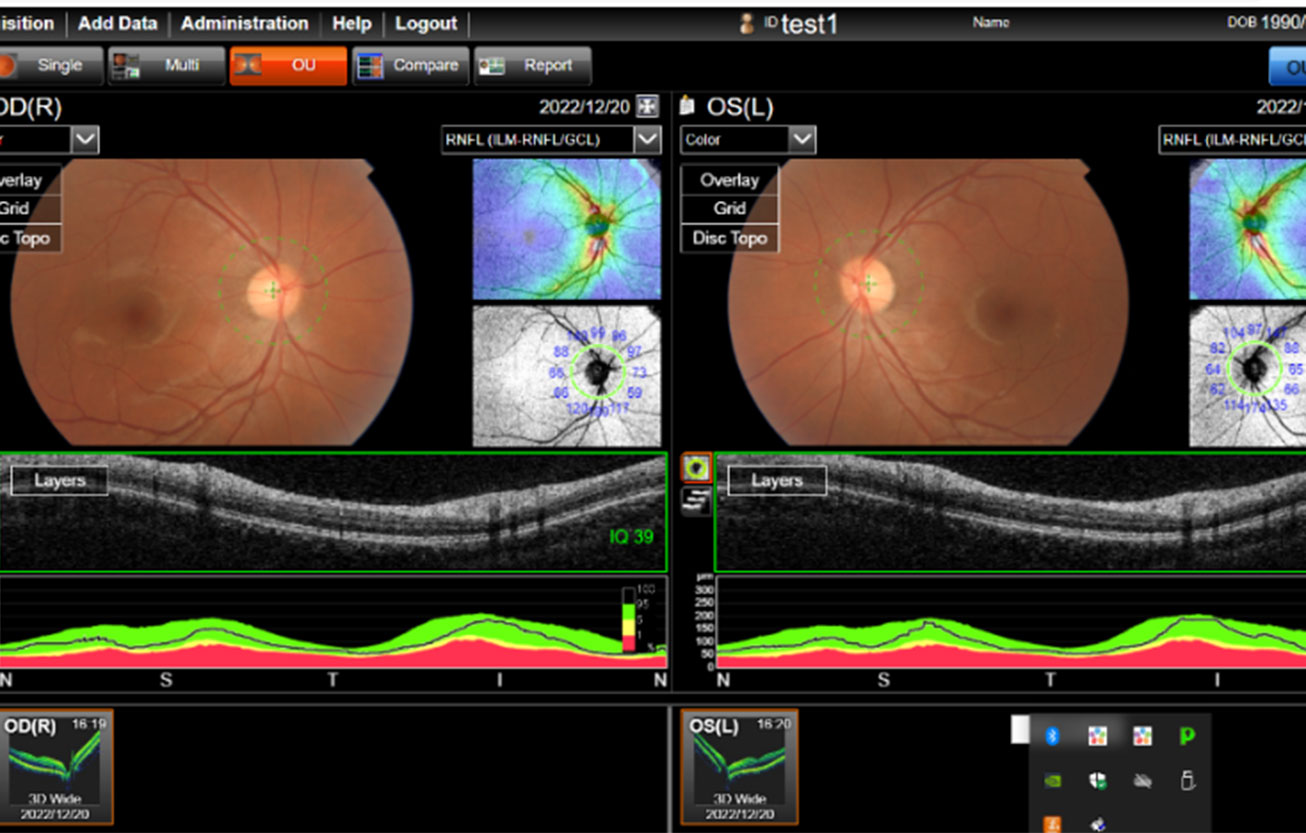

1.西塚弘一 先生(埼玉医科大学 医学部総合医療センター 眼科 教授)一般講演 「カラー眼底画像から糖尿病網膜症(DR)の判定とDR眼底所見を抽出する眼底AIの試作」

2.辻太郎 先生(帝京大学 眼科)一般講演 「Segment Anything Modelを用いた浮腫体積測定による加齢黄斑変性治療効果の測定」

3.三橋俊文 先生(帝京大学 視能矯正学科 教授)一般講演 「AIによるセグメンテーションを用いた近視眼脈絡膜厚の精密評価」

眼底画像AIで非常に多くの情報が得られるようになりました。眼底画像AIにMulti-Modality Explainable AIの技術を活⽤して、⾃施設向け高信頼性の診療支援AIシステムを、簡単に実現する方法を紹介します。

1.眼底画像AI:非常に多くの情報が得られ、高精度な予測が可能です。